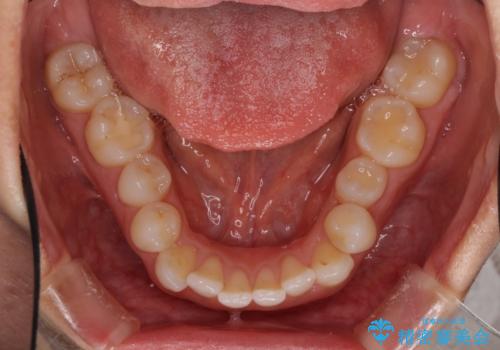

- 上下の前歯のデコボコと奥歯の反対咬合を気にして来院された患者様です。

インビザラインを用い、上下顎ともにIPR(歯と歯の間を削る)により叢生を改善することとしました。

奥歯の反対咬合は、骨格に由来するものであるため、改善できるところまで改善していくこととしました。